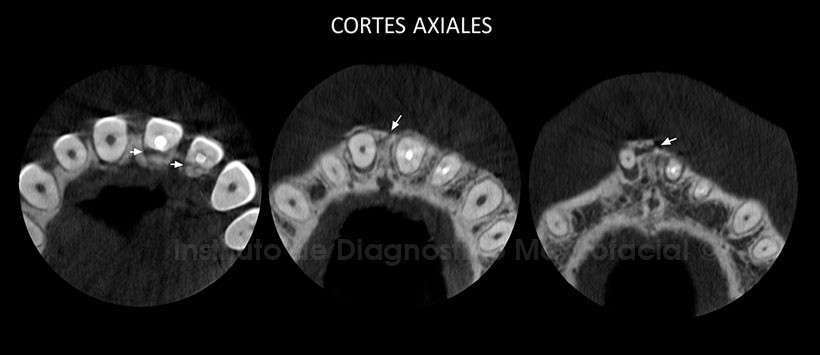

A la evaluación de la tomografía volumétrica (CBCT) en cortes axiales (Figura 2), transaxiales (Figura 3) y tangenciales (Figura 4) se observa trazo de fractura que compromete de la tabla ósea vestibular a nivel de la pieza 1.1, la corona se encuentra hacia palatino y el tercio apical se ubica fuera del lecho alveolar desplazado hacia vestibular.. Así mismo se aprecia fractura corono-radicular que compromete tercio cervical de la pieza 2.1 y fractura coronaria en la pieza 2.2.